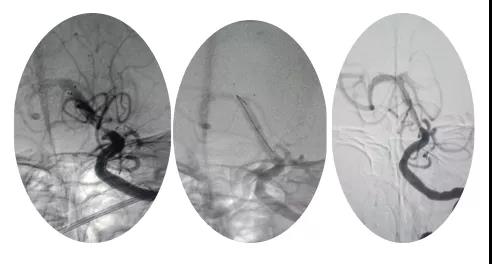

18:30手術(shù)開始,造影為基底動(dòng)脈閉塞,與患者家屬充分溝通,患者家屬同意給予介入取栓治療。共取栓2次,取出少量暗紅色血栓塊。造影示:基底動(dòng)脈有重度狹窄,結(jié)合患者病情演變及造影結(jié)果,考慮為動(dòng)脈粥樣硬化性狹窄。根據(jù)患者造影結(jié)果,目前單純?nèi)∷o法達(dá)到預(yù)期效果,決定給予基底動(dòng)脈支架植入術(shù)。根據(jù)患者基底動(dòng)脈直徑選擇3.0*13mm apollo球擴(kuò)支架,支架植入后造影示狹窄消失。

支架植入后患者神志轉(zhuǎn)清,四肢均可活動(dòng),左側(cè)肢體活動(dòng)略差于右側(cè),收入神經(jīng)內(nèi)四科病房進(jìn)一步治療。術(shù)后第三天患者神志清,四肢活動(dòng)基本正常,住院5天轉(zhuǎn)入當(dāng)?shù)蒯t(yī)院治療。?